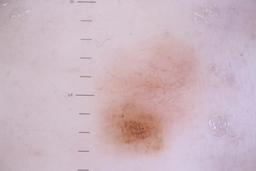

{

"acquisition_day": 211,

"age_approx": 45,

"anatom_site_general": "lower extremity",

"concomitant_biopsy": false,

"diagnosis_1": "Benign",

"diagnosis_confirm_type": "serial imaging showing no change",

"fitzpatrick_skin_type": "II",

"image_type": "dermoscopic",

"lesion_id": "IL_6061899",

"patient_id": "IP_5793596",

"sex": "female"